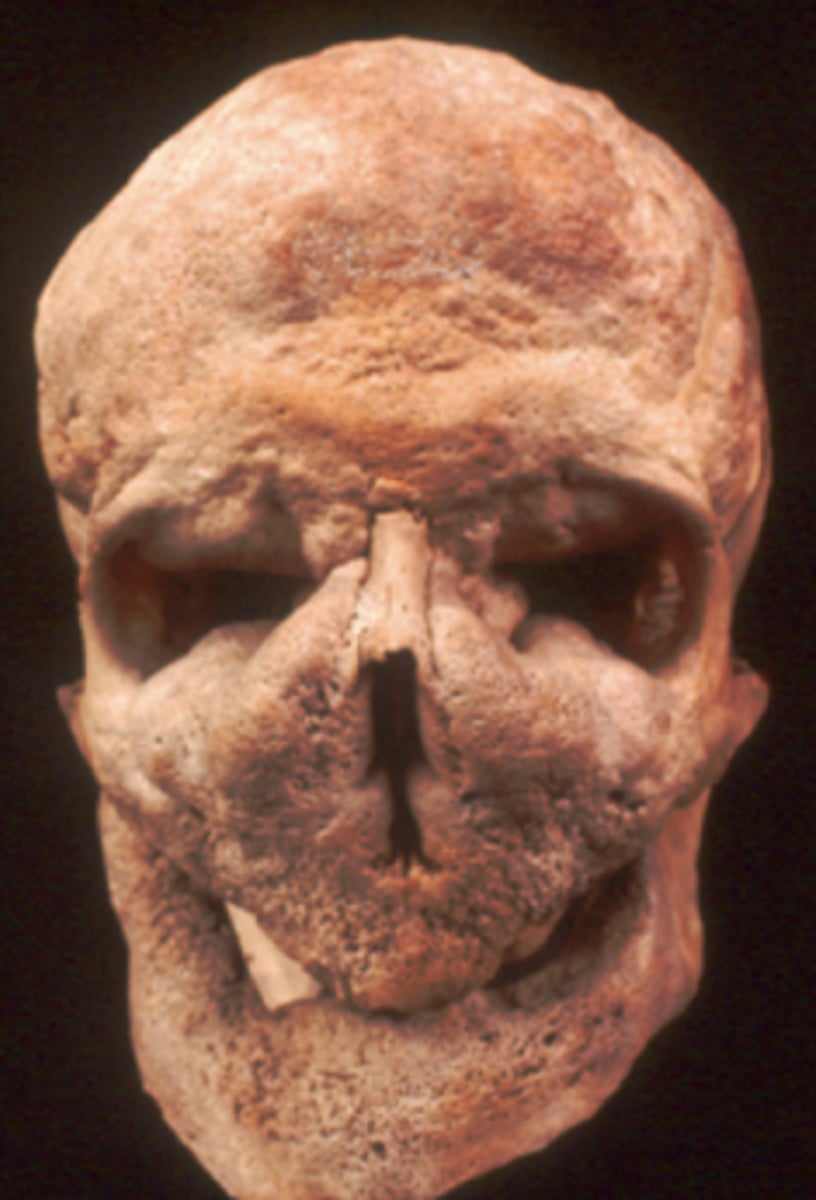

Leontiasis ossea

= Lion face

- Pagets

- Smashed in look centrally in face

- Thick ribs and vertebrae

- ~2% of cases become osteosarcoma